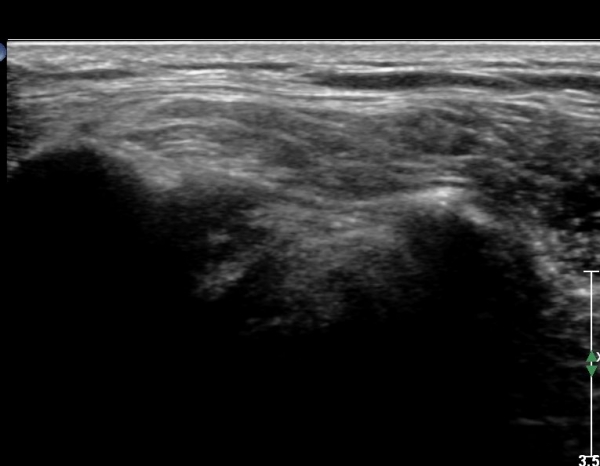

ÃÊÀ½ÆÄ ¼Ò°ß: ¿À±¸µ¹±â¿Í °ßºÀÀ» ¿¬°áÇÏ´Â ¿À±¸µ¹±â°ßº»Àδ밡 Á¤»óÀûÀÎ ¸ð½ÀÀ¸·Î °üÂûµÈ´Ù(»çÁø 1).

ŽÃËÀÚ¸¦ Á¶±Ý ¸»´ÜÀ¸·Î À̵¿ÇÏ´Ï ¿À±¸µ¹±â°ßºÀÀÎ´ë °ßºÀ ºÎÂøºÎ °ñ±ØÀÌ °üÂûµÇ°í ÀÎ´ë ½ÉÃþºÎ¿¡ ¼ö¾×Àú·ù°¡ ÀÖ¾î ¸¸¼ºÀûÀÎ Ãæµ¹À» ÃßÁ¤ÇÒ ¼ö ÀÖ´Ù(»çÁø 2).